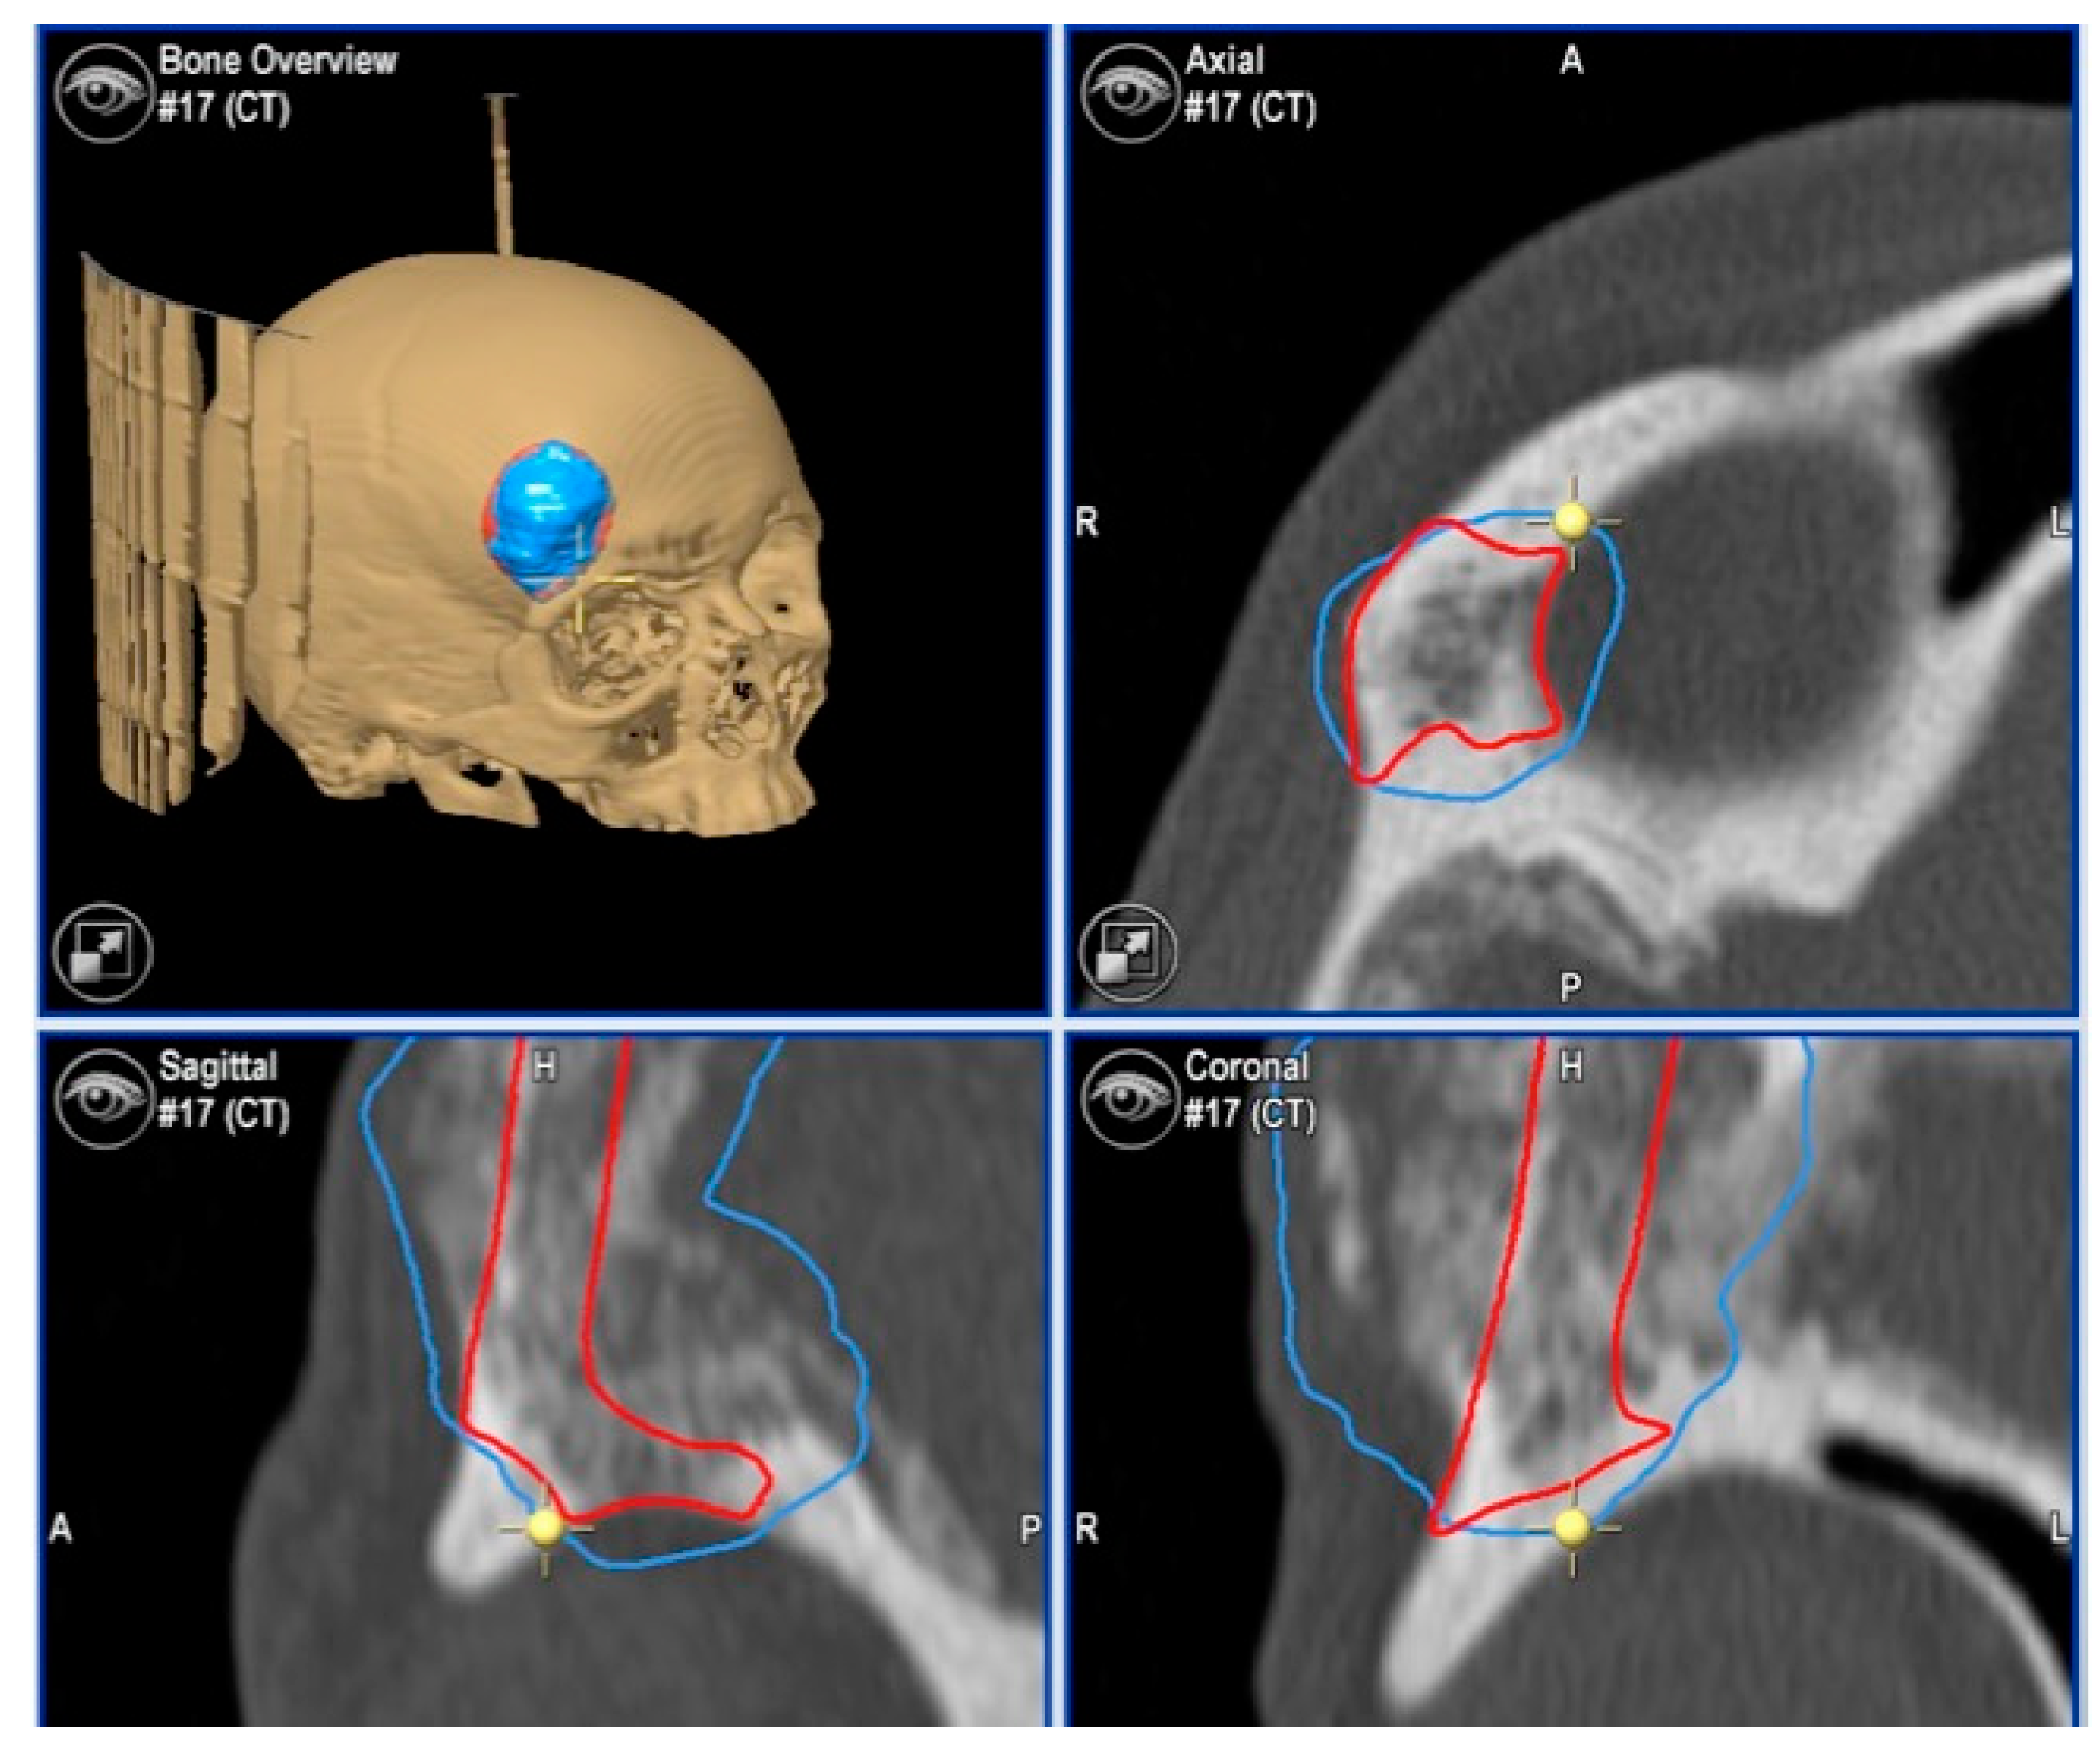

2.3.3. Surgical Navigation

- Metzger, M.C.; Hohlweg-Majert, B.; Schön, R.; Teschner, M.; Gellrich, N.C.; Schmelzeisen, R.; Gutwald, R. Verification of clinical precision after computer-aided reconstruction in craniomaxillofacial surgery. Oral Surg. Oral Med. Oral Pathol. Oral Radiol. Endod. 2007, 104, e1–e10. [Google Scholar] [CrossRef]

| 1 | 53/F | L/25 mm | Y | 4 mo | Dystopia | N | CT, MRI | Supraorbital rim, orbital roof | Intraosseous venous malformation | - | Resection + reconstruction | Y | Y | 1st, 2nd, 3rd | Coronal | Y | Piezoelectric device | N | PEEK prosthesis | 7 y/N |

| 2 | 54/F | R/33 mm | Y | 9 y | N | Y | CT, MRI | Frontal bone, orbital roof | Intraosseous venous malformation | - | Resection + reconstruction | Y | Y | 1st, 2nd, 3rd | Coronal | Y | Piezoelectric device | N | PEEK prosthesis | 6 y/N |

| 3 | 36/F | L/19 mm | Y | 6 mo | N | N | CT, MRI | Zygoma | Arteriovenous malformation | - | Resection + reconstruction | Y | Y | 1st, 2nd, 3rd | Transconjunctival + blepharoplasty + maxillary vestibular | Y | Piezoelectric device | N | PEEK prosthesis | 5 y/N |

| 4 | 47/M | L/30 mm | N | 2 y | N | N | CT | Zygoma | Intraosseous venous malformation | - | Resection + reconstruction | Y | Y | 1st, 2nd, 3rd | Transconjunctival + lateral canthotomy + maxillary vestibular | Y | Piezoelectric device | N | PEEK prosthesis | 6 y/N |